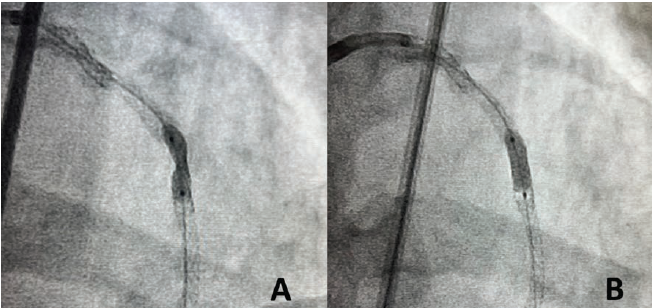

We planned on using the OPN NC super high-pressure balloon (SIS Medical AG) to expand the under-expanded stents. We attempted to perform optical coherence tomography (OCT) (Abbott Cardiovascular) of the LAD, but were unable to cross the more proximal area of stent under-expansion in the mid LAD (Figure 1, Letter A) with the OCT catheter. Next, we attempted pre-dilating, but despite a 7-French (F) extra backup 3.5 guide catheter, 7F guide extension catheter, and extra support guidewire, no balloon could be delivered across that lesion. We therefore performed laser atherectomy with an 0.9 mm laser (Philips) at 80 fluence and 80 pulses per second for a total treatment time of 180 seconds, facilitated by concomitant administration of 70% contrast to cross the proximal and mid lesions (Figure 1, Letters A and B). After laser atherectomy, we pre-dilated the LAD with a 2.5 mm x 20 mm semi-compliant balloon up to 20 atmospheres (atm). OCT of the LAD was performed, which despite pre-dilation, showed a minimal stent area (MSA) of 1.19 mm2 (Figure 2). We attempted to expand the lesion with a 2.5 mm x 12 mm noncompliant (NC) balloon at 22 atm, but this showed a significant waist (Figure 3). Dilation with a 3.0 mm x 10 mm OPN NC super high-pressure balloon at 35 atm, however, resulted in complete expansion of the under-expanded segment of stents (Figure 3). The remainder of the LAD was post-dilated with 4.0 mm and 3.5 mm NC balloons up to 20 atm. OCT was performed again, showing good stent expansion and an improvement in the stent area at the more distal lesion from 1.19 mm2 to 4.50 mm2 (Figure 2). Final angiography also showed a significant improvement in expansion of the LAD stents (Figure 4).